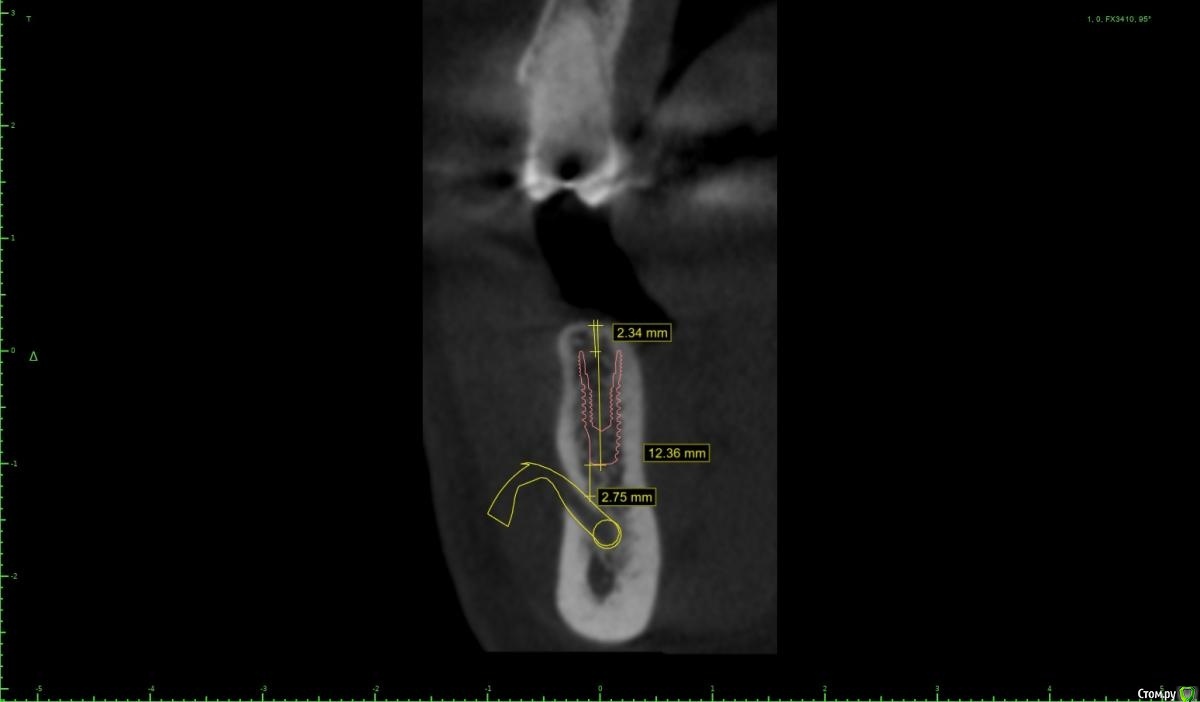

Женька Опубликовано 28 ноября, 2020 Поделиться Опубликовано 28 ноября, 2020 (изменено) Приветствую коллеги. В общем три недели назад 07.11.20 установил пациентке 2 имплантата в позиции 45-46. Гребень по ширине был около 6.5мм в области 4.5 и около 7.2мм в области 4.6 (с учётом заглубления на 1.5-2мм). Это была наверное первая имплантация во время которой я чувствовал себя спокойно и расслабленно. Всё прошло хорошо, немного покопался с непосредственным введением имплантатов, тк никак не хотели топиться на нужные 1.5мм. Поэтому пробовал методику с выкручиванием на пару витков и снова закручиванием. Особого толку не получил, потому взял финальную фрезу и чуть углублял ложе. Так несколько раз, тк боялся всё-таки немного что задену менталис и нлн. Ввиду того, что биотип у пациентки тончайший и язычно было совсем-совсем тонко - заглушки и швы. Назначил нпвс, ванны хг, аб терапию. Но на утро следующего дня пациентка сказала, что чувствует себя шикарно, решили что нпвс оставим, а аб терапию применять не будем (и грешу что в этом мою ошибка).Через неделю сняли швы, всё отлично.Спустя два дня после снятия начались какие-то "костные" боли, как говорит пациентка в области 4.5 импланта. Которые то отпускают, то снова наплывают. На 4.4 есть дефект твердых тканей (на фото виден), но судя по всему беспокоит не он .Пальпация вестибулярно в проекции 4.5 импланта болезненна, небольшая гиперемия, отёка нет. Гигиену пациентка запустила, тк боялась туда залезать и чистить. Снимки прилагаю первые два от 07.11, два последующих 28.11. Ну и внутри ротовые день операции и сегодняшние числа.Похоже 4.5 на выход? своими "туда-сюда" наверняка я нагрел всё что можно... снова расстройство в той работе, где накосячить предельно сложно... Добавка: пить аб ведь сейчас уже бесполезно? Изменено 28 ноября, 2020 пользователем Женька Ссылка на комментарий

колесников Опубликовано 28 ноября, 2020 Поделиться Опубликовано 28 ноября, 2020 (изменено) Имплант 13 мм? Зачем? При планировании видно, что он упирается апексом в кортикалку. По этому и поставить не могли сразу. Торк 45. Если имплант плотно контактирует с компактной пластинкой,она резорбируется окончато,со всеми вытекающими. Стоило выбрать имплант 8.5мм. Если притопили имплант,зачем поставили заглушку? Имплант зарастёт придётся выпиливать ,откапывать заглушку,ломать то что наросло непосильным трудом. Хороший торк-ставьте рабочий фдм. Сомнения-мелкий фдм или заглушка +1. Рекомендую сделать контрольный кт и поставить фдм Изменено 28 ноября, 2020 пользователем колесников 5 Ссылка на комментарий

Женька Опубликовано 29 ноября, 2020 Автор Поделиться Опубликовано 29 ноября, 2020 Я бы сейчас сделала три вещи :дала курс антибиотика шикарной женщине,гигиену навела бы во рту или хотя бы в этой области,депульпировала премоляр.Чтобы прикрыться со всех сторон. Выждать. Вынуть всегда успеется.А потом.. может,там уже формики просятся?Три недели, не рановато ли? По поводу премоляра, терапевта напрягу. А на каком режиме Вы закручиваете/выкручиваете?20оборотов на торке 30, далее руками динамометрическим ключом. Имплант 13 мм? Зачем? При планировании видно, что он упирается апексом в кортикалку. По этому и поставить не могли сразу. Торк 45. Если имплант плотно контактирует с компактной пластинкой,она резорбируется окончато,со всеми вытекающими. Стоило выбрать имплант 8.5мм.Импланты 10мм каждый, разметка на планировании - глубина препарирования с учётом заглубления. Проблема то как раз в области 4.5 импланта, там нет такого контакта с кортикой апикально, а область шейки хорошо развальцевал кортикальной фрезой. 4.6 где как раз контакт кортикальный спокоен. Если притопили имплант,зачем поставили заглушку? чтобы избежать проблем как в предыдущем моём случае, где тоже было тонко язычно. Потому хотел на этапе раскрытия работать с десной и язычно перемещать объём. http://forum.stom.ru/topic/40254-otsrochennaia-implantatciia/ Сомнения-мелкий фдм или заглушка +1. что значит заглушка +1? Если сейчас залезть и выкрутить заглушки не велики ли риски прокручивания имплантата...ведь на 3-5 недели самая большая потеря первичной стабильности происходит. Ссылка на комментарий

Женька Опубликовано 14 декабря, 2020 Автор Поделиться Опубликовано 14 декабря, 2020 (изменено) Наконец-то получил КТ от пациентки...Боли значительно уменьшились, практически не беспокоит... Коллеги, что думаете? Я так понимаю это уже не фон от титана? и вердикт всё-таки один? Сам склоняюсь всё-таки более к понаблюдать. Вестибулярно конечно очень тонко Толщина была ~ 6.7мм Изменено 14 декабря, 2020 пользователем Женька Ссылка на комментарий

Irouil Опубликовано 14 декабря, 2020 Поделиться Опубликовано 14 декабря, 2020 Ну и где тут язычно передавленная кортикалка? Меня смущает только картина в области верхушки симптомного винта, ну и заглубление Я бы дождался уже срока интеграции Ссылка на комментарий

Женька Опубликовано 14 декабря, 2020 Автор Поделиться Опубликовано 14 декабря, 2020 Ну и где тут язычно передавленная кортикалка? Меня смущает только картина в области верхушки симптомного винта, ну и заглублениеНе знаю, я про язычную кортику не говорил. Меня тоже смущает... и в области соседа такого фона (а это не фон я уверен) нет... А с заглублением что не так? по прицелам там 1.5-2мм, на кт почему-то этих мм вообще нет и как будто крестально стоят Ссылка на комментарий